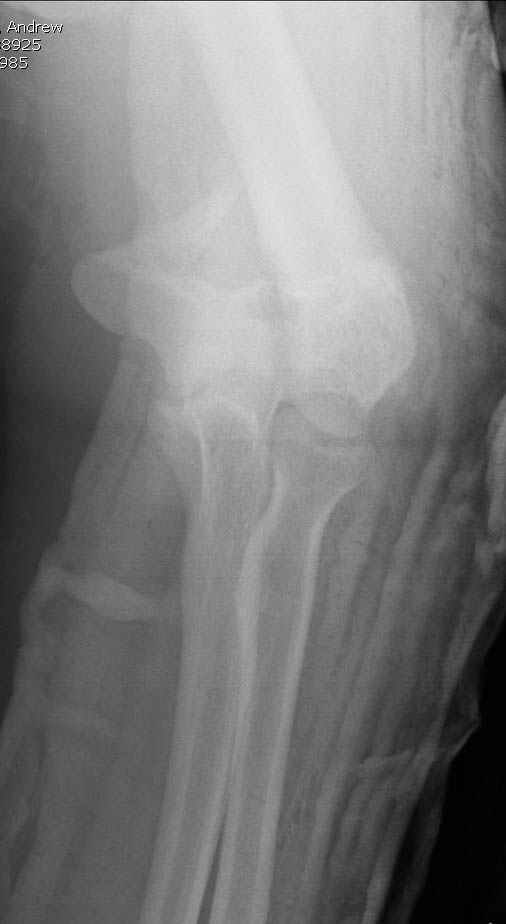

Примерный случай, только перелом был открытый, в задне-медиальной стороне рана около 2 см по характеру "изнутри кнаружи", неврологический статус со слабостью сгибания мизинца, также слабая абдукция и аддукция указательного пальца и сгибания в кисти.

Больному сделали обработку и наложили временный аппарат внешной фиксации плечо-предплечье.

На шестой день сделали открытую репозицию чрезлоктевым доступом двумя locking plate, локтевой нерв был ушибленным, после операции положительная динамика в Flexor Carpi Ulnaris. Фиксацию локтевого отростка произвели tension band technique с дополнительным шурупом.

Этапы операции на снимках....